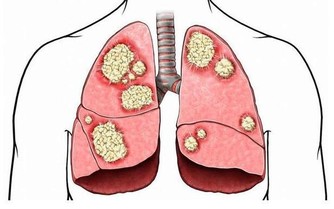

皮膚瘙癢、有異味:腎病

腎臟功能出現問題,無法排出的廢棄物質,導致皮膚受到刺激,不僅會瘙癢難耐、乾燥無光,還可能出現尿腥等異味。